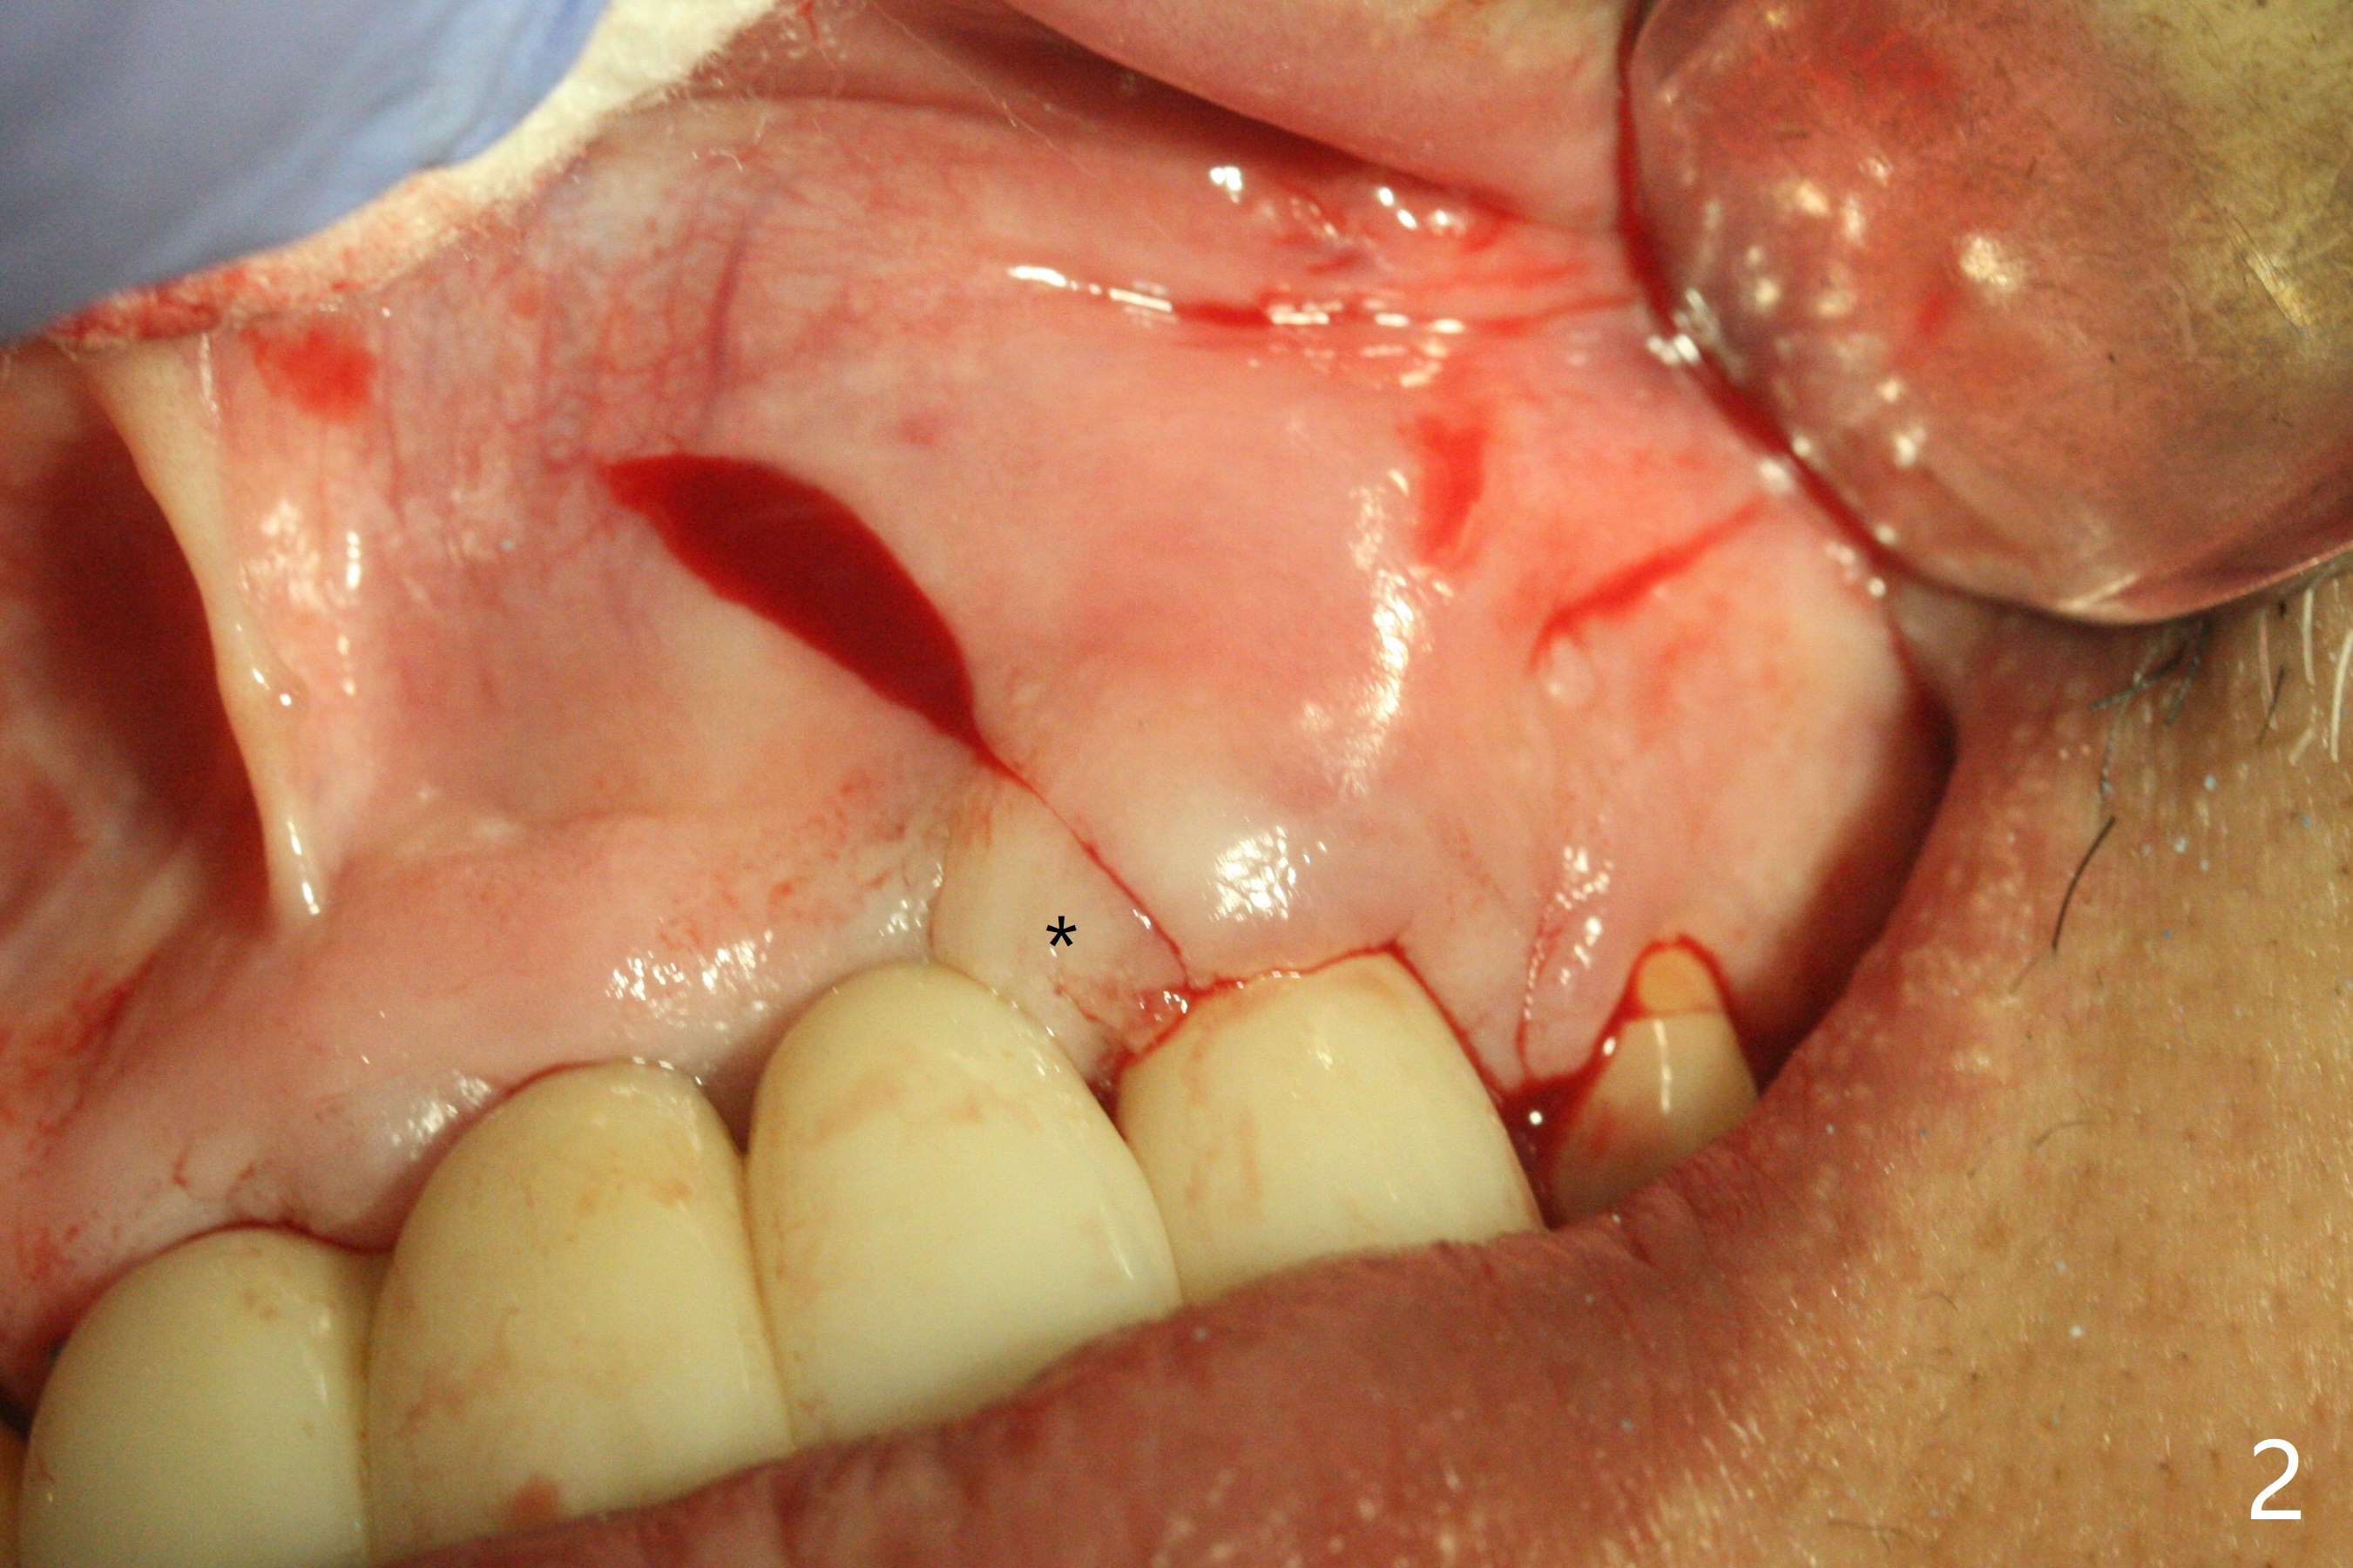

There is no obvious black triangle between the implants at #8-11 (Fig.1 post infiltration). Following papilla (Fig.2 *) sparing incision and elevation of the buccal flap, the fenetration of the buccal plate around the socket shield (Fig.3 S) is found at #11; there is a distal defect with granulation tissue (*). After shield and granulation tissue removal, the coronal implant is found exposed (Fig.4 until osteotomy). The relatively flat surface of IBS implant is apparently less likely to develop periimplantitis. With periosteal relief and placement of sticky bone (Fig.7 *), PRF and 6-month membrane, the wound is closed with 4-0 PTFE suture (Fig.5). Failure of socket shield is related to retention of the apex (Fig.6 <). Probe before extraction and remove apex and gutta percha. There appears no buccal or palatal (P) defect 9 months post shield removal (17 months post cementation, Fig.8), although the bone density palatally is low. Although the sagittal section (Fig.9 (lower left panel) shows the absent palatal plate at #10, the 3-D image and the coronal section do not (upper let and right panels). The 2.5 mm implant at #9 appears to have been placed buccal (Fig.10 B), although the buccal crest is present. In contrast the 2.5 mm implant at #8 appears within the bone boundary (Fig.11). The soft tissue remains healthy at #8-11. Bone graft will be done if needed.